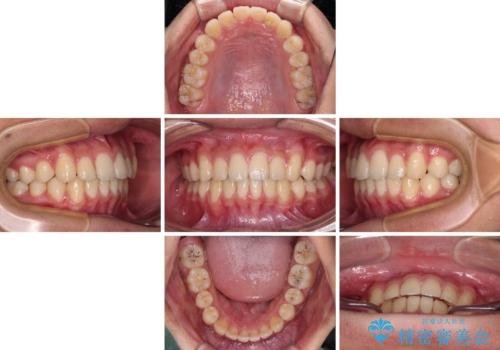

- 前歯のデコボコと隙間を気にして来院された高校生の患者様です。

下顎前歯が上顎前歯を突き上げるような咬み合わせとなっており、その影響で上顎正中に隙間ができている状態でした。

叢生の程度は軽度であり、本人もしっかりと使用する自信があるとのことだったので、インビザラインによる矯正治療を行うこととしました。

突き上げによる隙間を予防する為に、深い咬み合わせを改善するような治療計画としました。咬み合わせを改善させることはできましたが、隙間は後戻りしやすいので、通常の下顎前歯のみではなく、上顎前歯2本もワイヤーで保定を行いました。